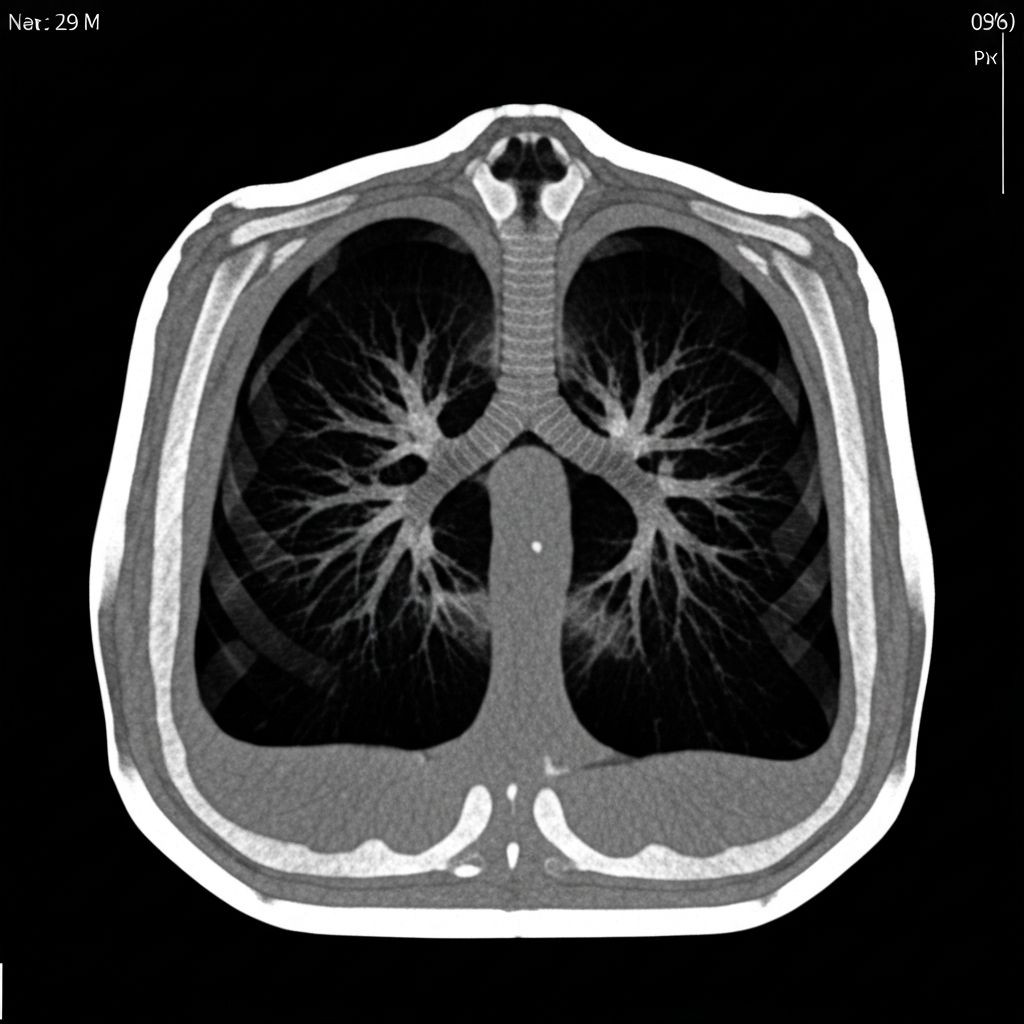

CT CHEST 2025

SLICE 47/128

ZOOM 1.2x